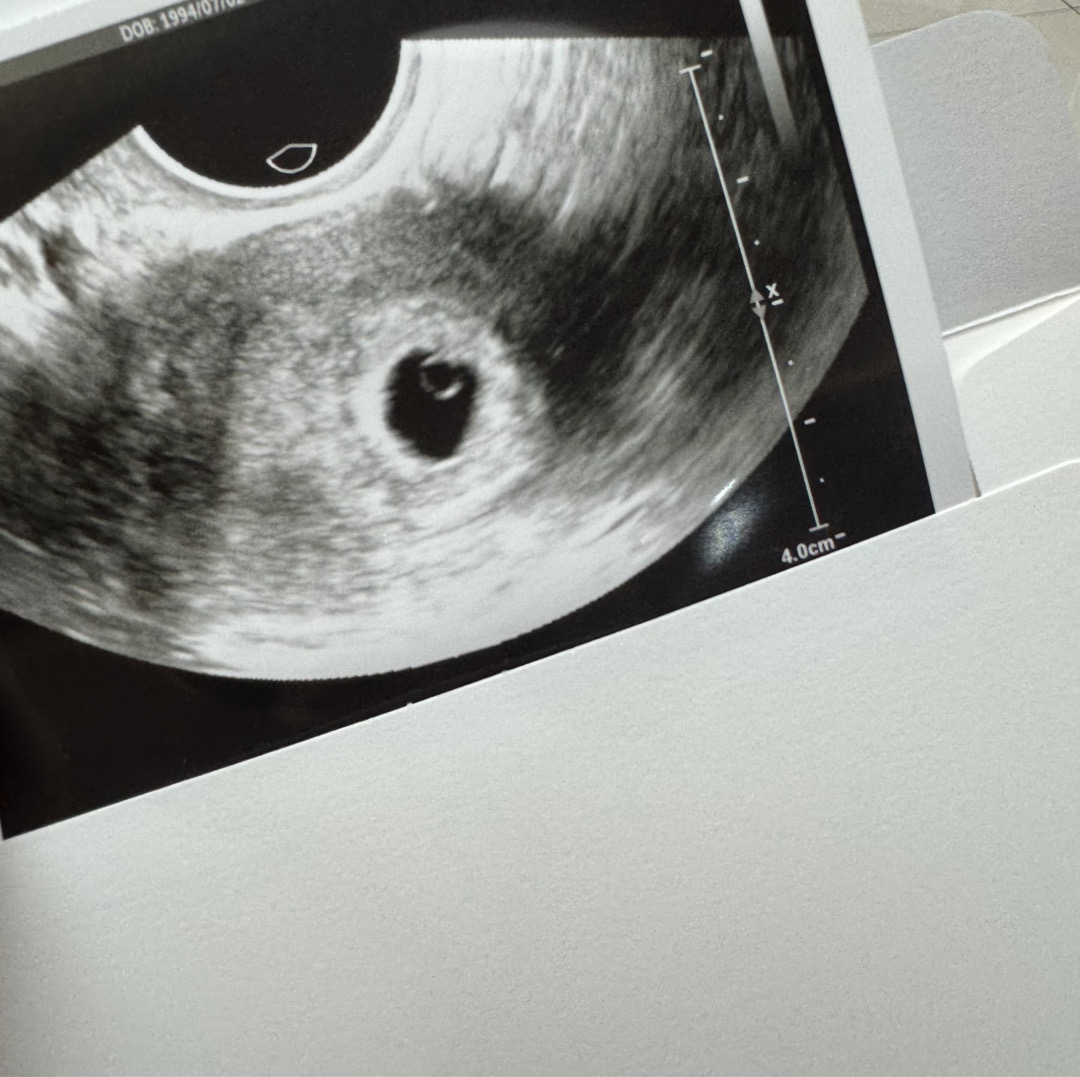

5주 2일차 초음파 보고 왔어요-!

5주 2일차 초음파에 아기집과 난황 다 보고왔어요..!!🤍 다음주에는 심장소리 들으러 오라고 하셨습니다-! 몽글몽글해요…🫧

저는 1cm 였어요!!